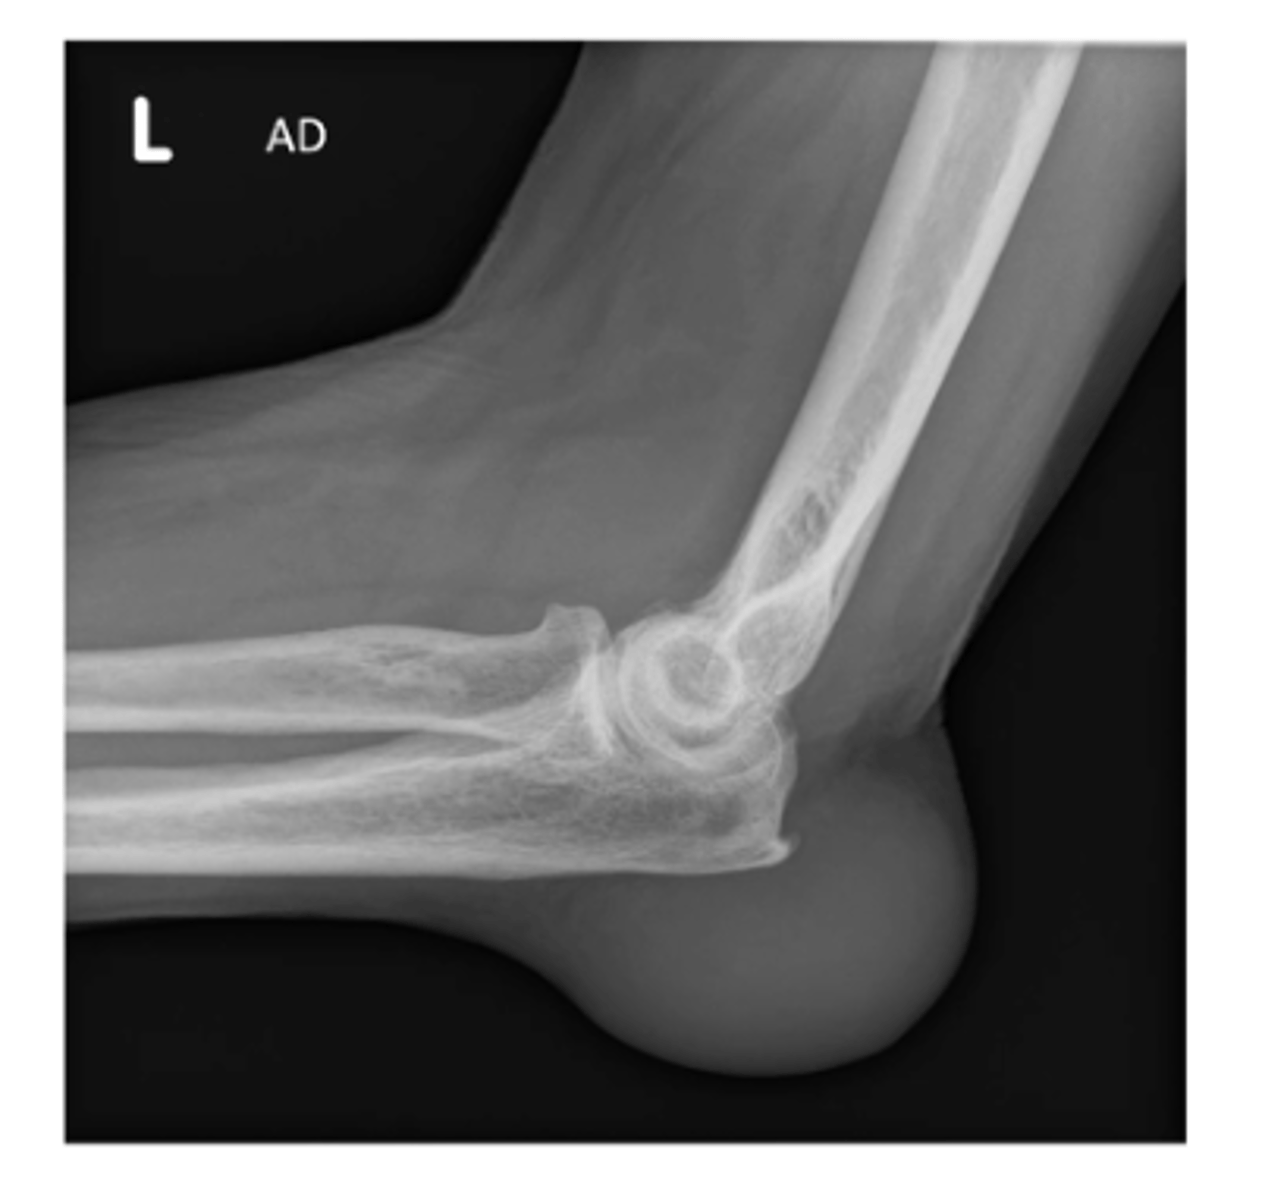

S: soft tissue...olecranon bursitis (typically caused by trauma or patients wearing slings due to the rubbing/friction)

Describe the MOST obvious "ABCS" component.